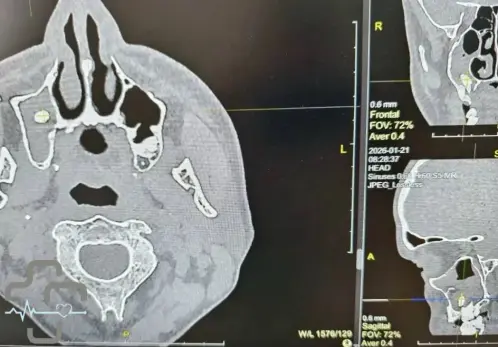

В хирургическое отделение городской больницы Орска поступил мужчина с необычной проблемой. После удаления зуба, он оказался в носовой пазухе.

Оказывается такое случается: во время удаления зуба может произойти нарушение целостности костной перегородки, отделяющей зубы от носовой пазухи. В редких случаях зуб или его фрагменты попадают в пазуху, что приводит к закупорке и развитию воспаления. В этом случае зуб проник так глубоко, что мужчина с трудом дышал.

Зуб был глубоко вклинен в пазуху, что усложняло извлечение и вызывало проблемы с дыханием. После успешной операции дыхание пациента восстановилось, а риск осложнений был исключен.